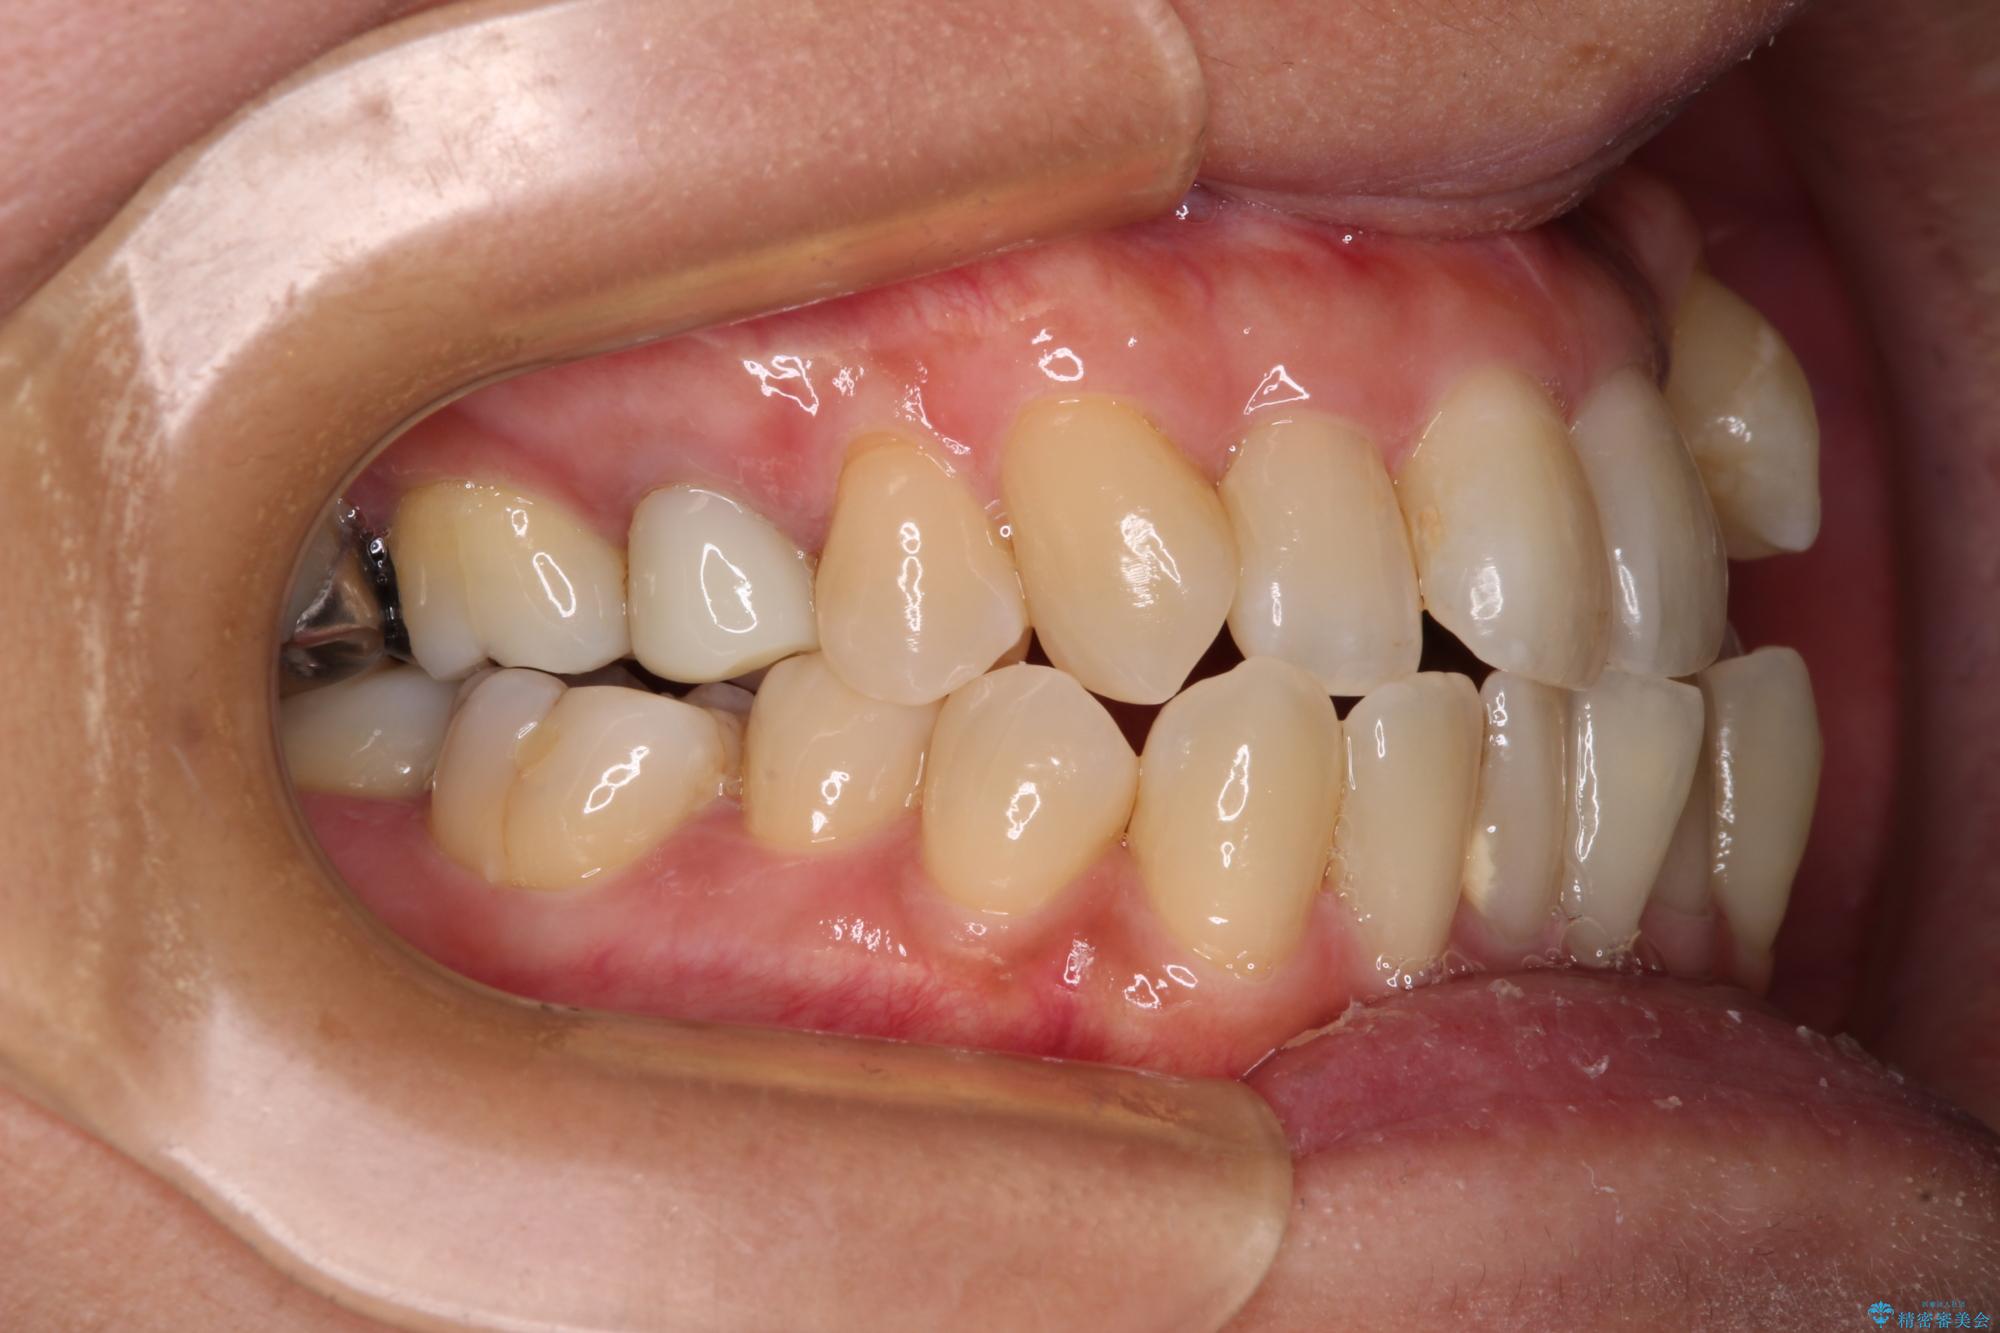

- 前歯のデコボコや八重歯を治したいとのことで来院された患者様です。

受け口傾向の骨格であり、前歯はクロスバイトまたは切端咬合となっており、下顎を中心に歯列全体の後方移動を行い、IPR(歯と歯の間を削る)によってデコボコが解消するように設計し、インビザラインにより治療を行うこととしました。

受け口傾向のインビザライン矯正は比較的治療を行いやすいため、きれいに仕上げることができました。舌の突出癖が顕著であったため、改善のためのトレーニングをしっかりと行っていただきました。